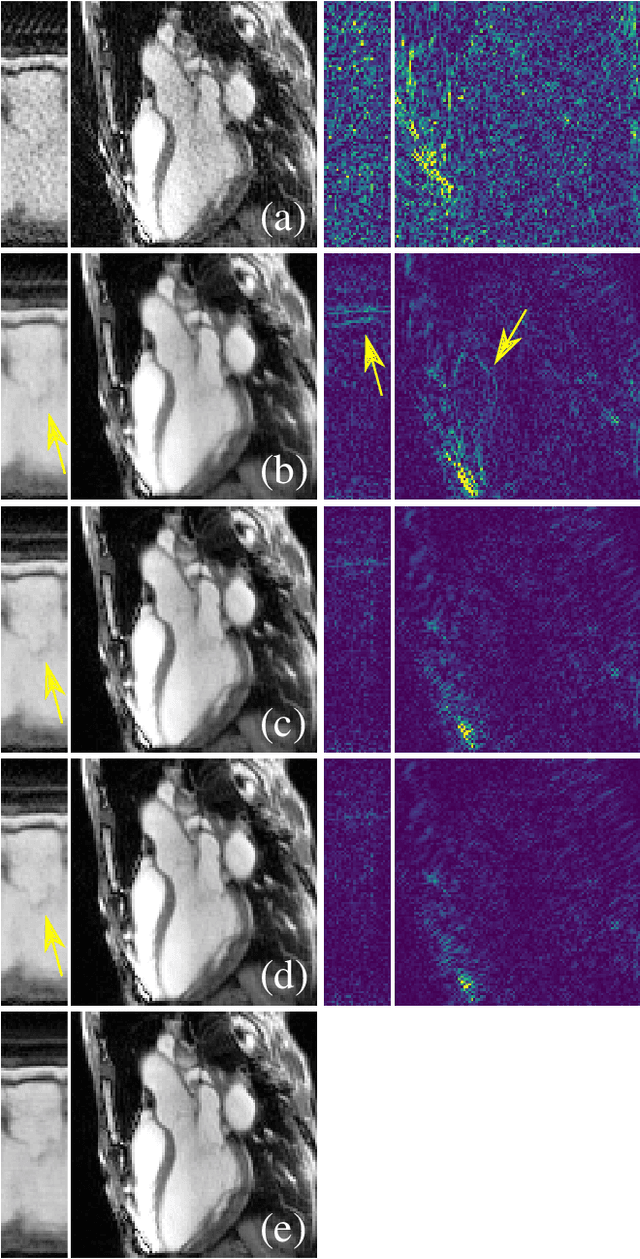

Abstract:The concept of sparsity has been extensively applied for regularization in image reconstruction. Typically, sparsifying transforms are either pre-trained on ground-truth images or adaptively trained during the reconstruction. Thereby, learning algorithms are designed to minimize some target function which encodes the desired properties of the transform. However, this procedure ignores the subsequently employed reconstruction algorithm as well as the physical model which is responsible for the image formation process. Iterative neural networks - which contain the physical model - can overcome these issues. In this work, we demonstrate how convolutional sparsifying filters can be efficiently learned by end-to-end training of iterative neural networks. We evaluated our approach on a non-Cartesian 2D cardiac cine MRI example and show that the obtained filters are better suitable for the corresponding reconstruction algorithm than the ones obtained by decoupled pre-training.

Abstract:In this work, we propose an iterative reconstruction scheme (ALONE - Adaptive Learning Of NEtworks) for 2D radial cine MRI based on ground truth-free unsupervised learning of shallow convolutional neural networks. The network is trained to approximate patches of the current estimate of the solution during the reconstruction. By imposing a shallow network topology and constraining the $L_2$-norm of the learned filters, the network's representation power is limited in order not to be able to recover noise. Therefore, the network can be interpreted to perform a low dimensional approximation of the patches for stabilizing the inversion process. We compare the proposed reconstruction scheme to two ground truth-free reconstruction methods, namely a well known Total Variation (TV) minimization and an unsupervised adaptive Dictionary Learning (DIC) method. The proposed method outperforms both methods with respect to all reported quantitative measures. Further, in contrast to DIC, where the sparse approximation of the patches involves the solution of a complex optimization problem, ALONE only requires a forward pass of all patches through the shallow network and therefore significantly accelerates the reconstruction.